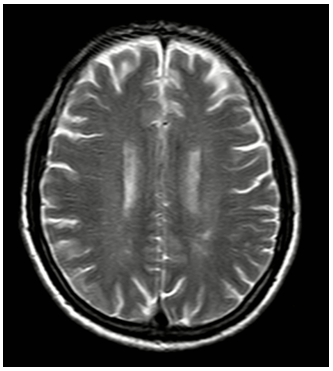

MRI sọ não:

Hình 3: MRI sọ não chưa phát hiện tổn thương thứ phát